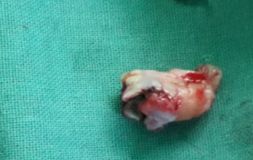

PROCEDURE FOR WISDOM TOOTH EXTRACTION

The tooth removal process depends upon the stage in which the wisdom teeth is. It is easy to extract wisdom tooth if it has fully erupted. But if the tooth is impacted then it will require an incision in the gums. Usually, the tooth is extracted in parts to minimize the amount of bone required to be extracted for tooth removal.